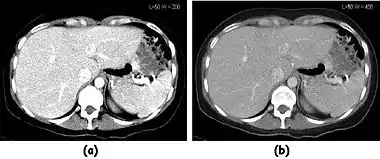

Fig. 7.15.2: Effect of window width and level on CT image display: (a) Level = 50; Width = 200. (b) Level = 50; Width = 400. The image in (a) is displayed with greater contrast and appears noisier than that in (b).

Examples of image display manipulation are shown in the two figures above. In Figure 7.15.2, the same image of a slice through a patient's liver is displayed using a relatively narrow window (high contrast) and also with a wide window. The image with the narrower window appears noisier, but this is merely a reflection of the fact that the gray scale is spread over a narrow range of CT-numbers.